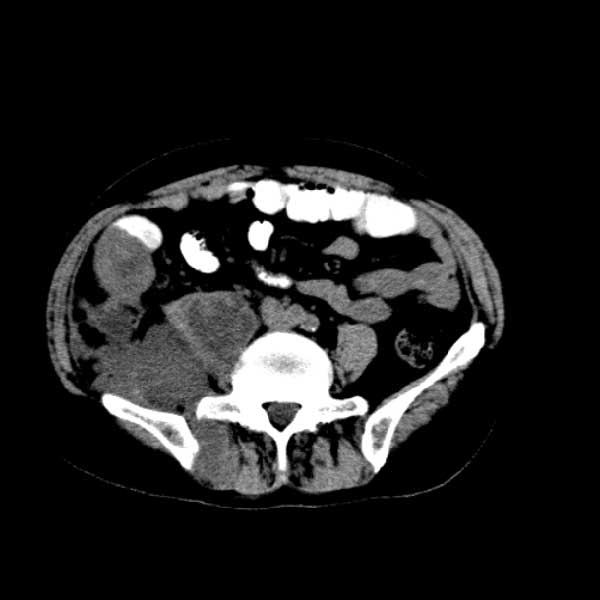

标题: CT13513:男 71 腹部疼痛20余天,近几天高热就诊,骨窗未见异 [打印本页]

标题: CT13513:男 71 腹部疼痛20余天,近几天高热就诊,骨窗未见异

考虑感染性病变可能性大,起源于阑尾?

感染,脓肿形成

考虑为化脓性阑尾炎.脓肿形成.及多肌肉累及.

考虑右侧腰大肌脓肿,向右髂窝、右腹股沟流注。

支持化脓性阑尾炎伴右髂窝脓肿、腰大肌腰方肌脓肿形成。

考虑腹腔及盆腔化脓性炎症,累及右侧髋关节及腹股沟区.

首先考虑化脓性阑尾炎伴腰大肌、腰方肌脓肿,不除外回盲部结核。

回盲部癌待排除。

患者肠镜检查考虑结肠癌,病理证实

患者肠镜检查考虑结肠癌,病理证实。肺部ct可见多发结节,考虑转移